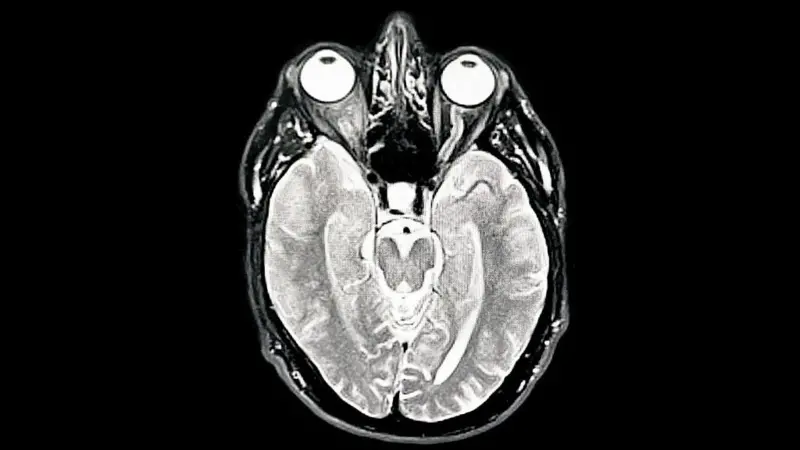

Santo Domingo.- El cerebro es mucho más que el órgano del pensamiento. Es, según el neurocirujano José Joaquín Puello, el verdadero centro del amor, de la conciencia, del comportamiento humano y también el escenario donde se libran algunas de las batallas más silenciosas y mortales de la salud moderna.

Desde la mirada del neurocirujano, el cerebro es también un órgano sorprendente en lo físico.

“Es rosado, bellísimo, late… y es más caliente que el cuerpo”, describió.

Según explicó, la temperatura cerebral ronda los 38.5 grados Celsius, debido a su enorme consumo energético.

“El cerebro consume el 20 % de toda la energía que produce el cuerpo. Consume más que el corazón, el hígado o los intestinos”, afirmó en una entrevista.